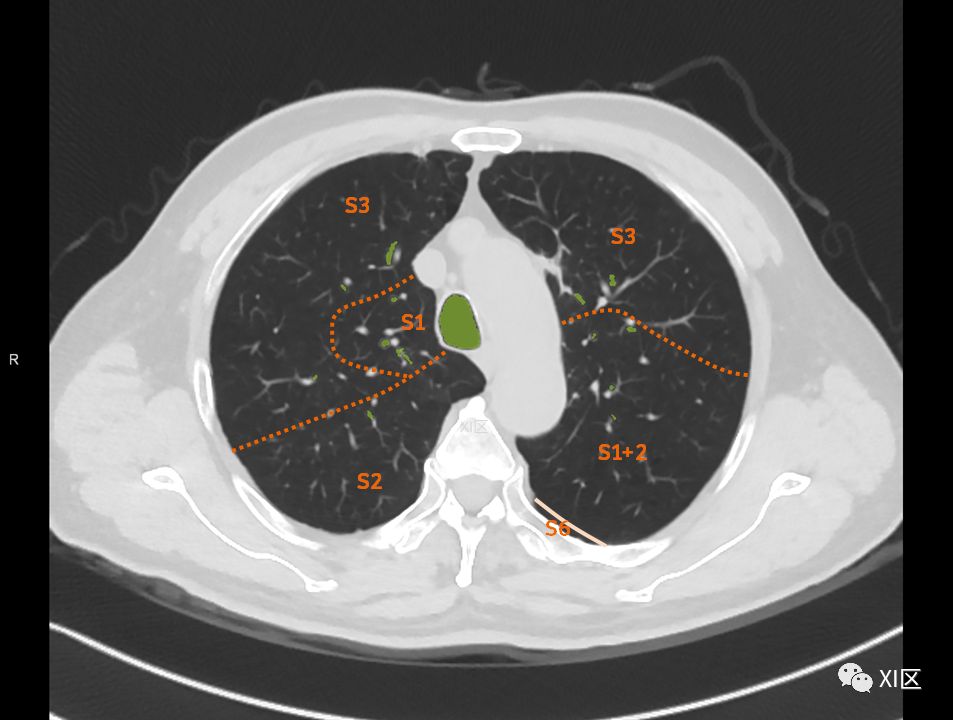

在进行肺的分段时,可以上下观察浏览,沿着相应气管的走形可以更容易准确地进行分段。

肺的分段

肺的断层分段示意图